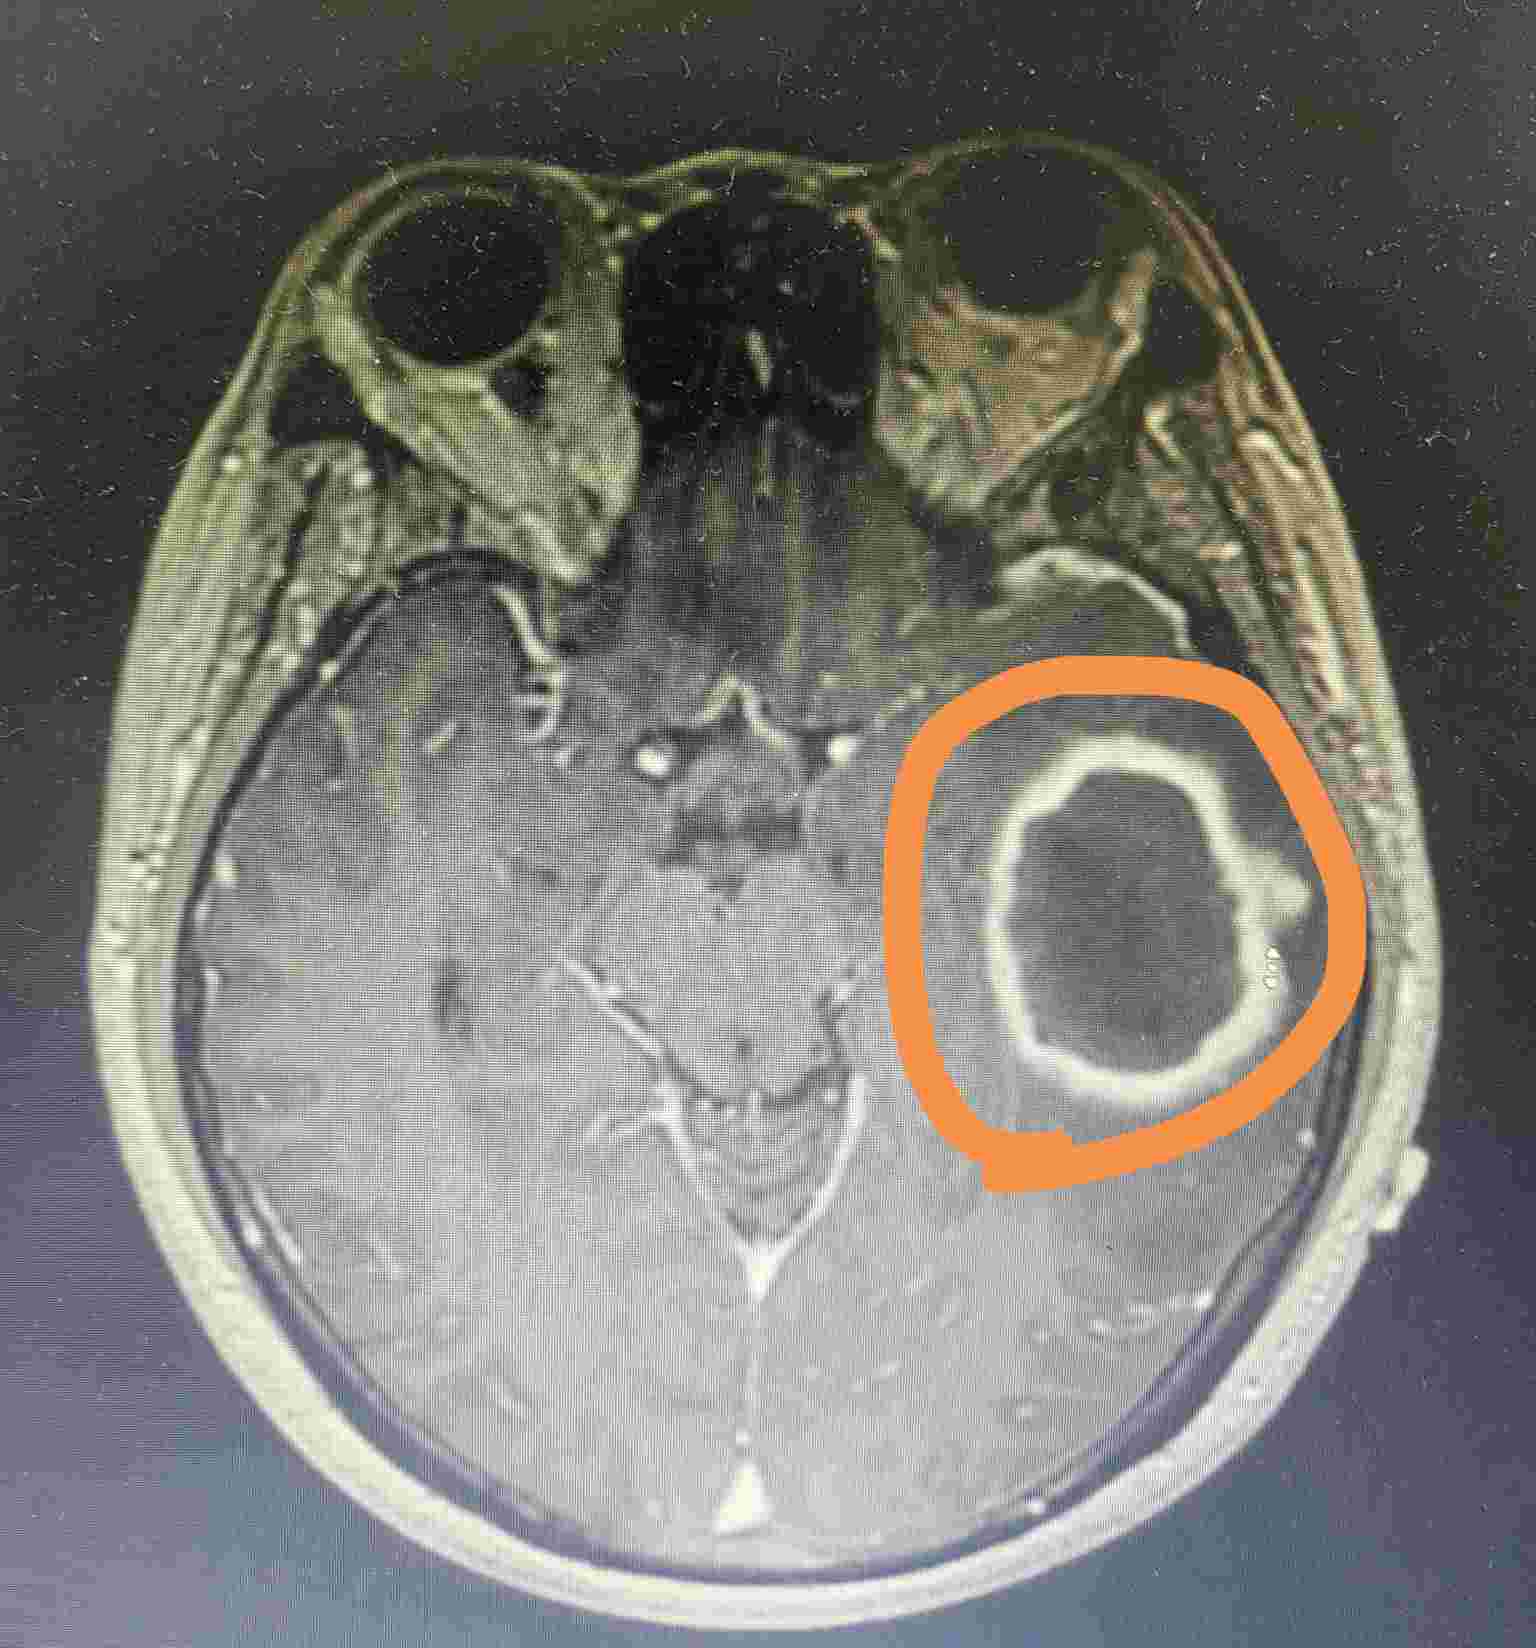

颅内脓肿图片(橙色圆圈内)

最近病房收了一位50岁的大姐,因为突然发热、头痛、呕吐起病入院。入院后查磁共振发现脑脓肿。经过感染科医生的仔细询问,患者发病前曾有牙痛病史。当时考虑是一个牙源性感染。

随后患者转入神经外科做了手术切除病灶,脓液培养出来了“咽峡炎链球菌”,这是一种口腔的常见定植菌,也再次证实了脑脓肿可能是牙源性来源。